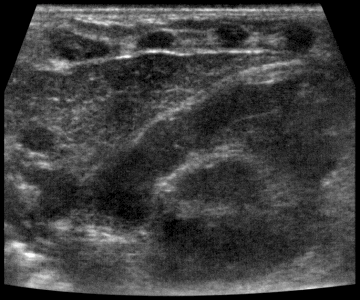

Тимус - киста, B-режим

[EN] Эхограмма №736: Киста тимуса (левой доли) у ребенка 2 лет. Микроконвексный датчик 4-9 МГц (неонатальный), двойной B-режим (слева - продольно, справа - поперечно).

Автор: Суханов С.А., Саратов.

Изображение получено с помощью УЗ сканера H60 (снят с производства).